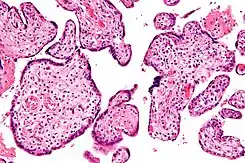

Micrografía de vilitis de etiología desconocida. Tinción H&E.

Histomorfológicamente, la VUE se caracteriza por un infiltrado linfocitario de las vellosidades coriónicas sin una causa demostrable. Las células plasmáticas deben estar ausentes; la presencia de células plasmáticas sugiere una etiología infecciosa, por ejemplo, infección por CMV